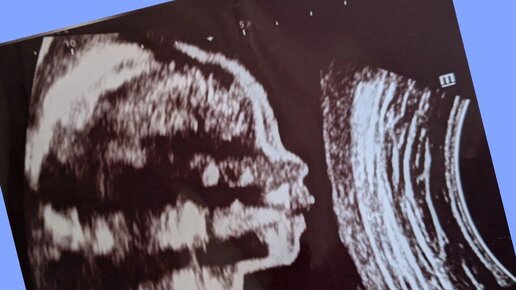

На каком сроке можно узнать пол ребенка и как: 6 доступных способов

Покажет ли УЗИ на ранних сроках беременности пол будущего малыша? Говорят ли правду аптечные тесты? И как еще можно узнать, кто же все-таки у тебя родится. Предупреждаем, некоторые способы могут вызвать осложнения. Методы определения

1. Ультразвуковое исследование (УЗИ)